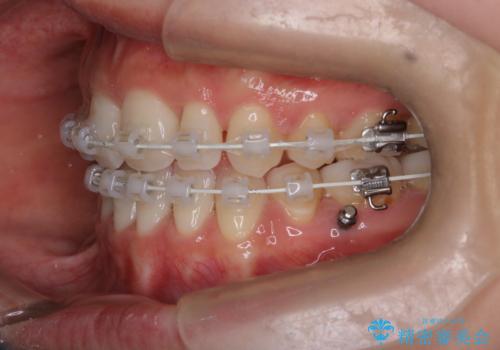

- 矯正装置

- 審美装置

- 2年5ヶ月

- 10-30回

- 口元をさげたいという主訴で来院されました。4番の歯を4本抜歯し、遠心移動とIPRをしました。右上2番が矮小歯のため見た目を重視するならクラウンの提案をしましたが、そのままでの治療を希望されました。

矯正治療の最終段階でスペースクローズにやや時間がかかりましたが、前歯が下がったことで口元の位置も下がりきれいになりました。